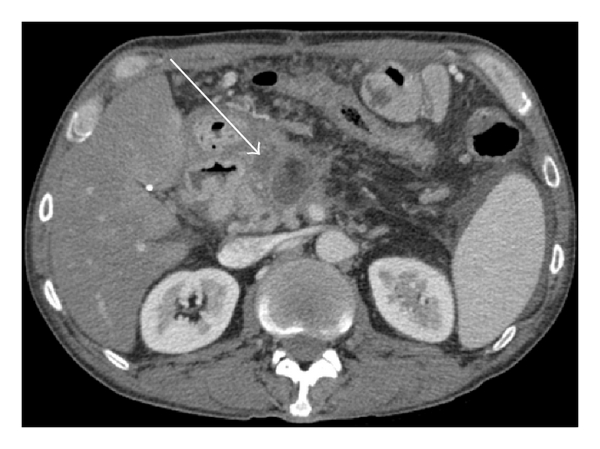

As Figures 1–5 demonstrate, the immediate postablation bed and zone are invariably larger than the original ablated tumor. We remain descriptive because the entire bed was extremely difficult to measure owing to the amorphous, irregular nature of the ablation. Moreover, the ablated tissue is not within an encapsulated organ; therefore, the ablation zone does not have defined borders as seen after, for instance, liver ablation. Four patients that showed continued stable disease are highlighted in Figures 1 through 4. An amorphous, hypoattenuating region with irregular shape persisted in subsequent CT scans in all patients with “stable disease.” Moreover, the ablation zone was typically smaller (due to decreased edema, hyperemia, and granulation tissue) than the immediate postablation bed in the following months and remained stable provided there was no recurrence. Imaging findings demonstrating recurrence are shown in Figure 5. Along with persistent irregular shape the ablation zone showed increased tumor bulk and extension as well as new mass effect (new narrowing of a blood vessel). Enhancement of the ablative bed was variable and often showed increased enhancement in the three-month and longer follow-up images. This was felt to be related to development of granulation tissue and fibrosis.

In our study, we found that the postablation bed is larger in volume than the initial mass. This is expected because it contains the tumor and the ablative margin. The postablation bed and zone appear irregular, amorphous, and hazy without margins or true boundaries. The ablation zone may decrease in size from the initial post-op bed to the initial surveillance study as the surrounding edema/fluid and inflammation resolve revealing the true ablation zone; however, as mentioned above, since there have been reports of an ongoing apoptotic process that persists up to 6–8 weeks after ablation, it will not be unusual to see some increase in volume in surveillance [19, 20]. Therefore, size is considered secondary in the CT evaluation for this reason and because the postablative bed/zone has poorly defined margins, making objective imaging assessment (size, attenuation) cumbersome. This may undoubtedly affect the accuracy and reproducibility of the measurement. Nonetheless, any increase in volume after stabilization of the postablation zone is considered worrisome for recurrence (Figure 5).

Other clues that may suggest recurrence are any new encasement or narrowing of adjacent vessels or any subjective extension of soft tissue outside the boundaries of the previously established baseline ablation zone. However, in patients that have undergone prior radiation therapy or undergo post-IRE radiation therapy, persistent isolated narrowing (without other worrisome findings) is not always recurrence and must be followed with serial imaging, clinical evaluation, and CA19-9 serum tumor markers. Vessels within and adjacent to the ablation bed may show narrowing immediately after the procedure, but this should resolve or at least remain stable in subsequent studies. Often, if narrowing of a vessel is seen with the index tumor it will often persist after ablation. For equivocal cases, PET/CT may play a role in differentiating postablative changes from recurrence [25].